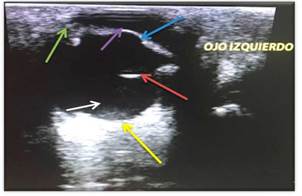

Comparando con el caso clínico, y de acuerdo a lo reportado en la bibliografía se puede observar que el ojo izquierdo está ecográficamente normal (Figuras 10 y 11), ya que se identifican todas las estructuras anatómicas normales, sin ningún tipo de alteración.

En las (Figuras 12, 13 y 14) se aprecia cómo a través de la ecografía se logra evidenciar un tumor intraocular que daña la estructura anatómica, mediante una imagen heterogénea en el cuerpo ciliar.

De acuerdo a lo anterior, en el ojo derecho del paciente, se observa gracias a la ecografía, una masa con una densidad heterogénea, bien definida en el cuerpo ciliar derecho (Figura 14), insinuante de una neoplasia a nivel uveal, como diagnóstico.